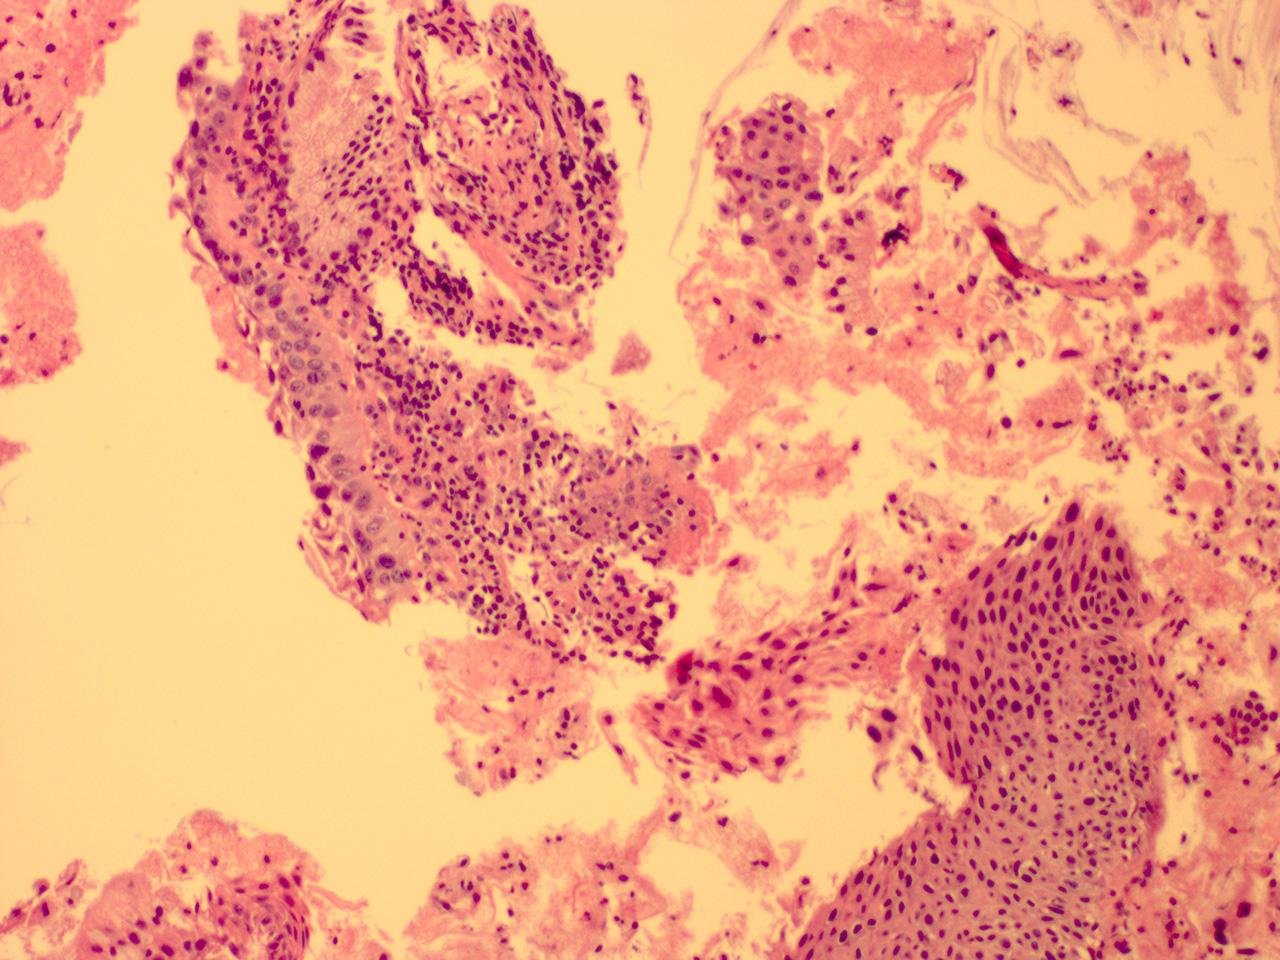

![]() Case 3

Soft Bx CIN 3

40x - High Power |